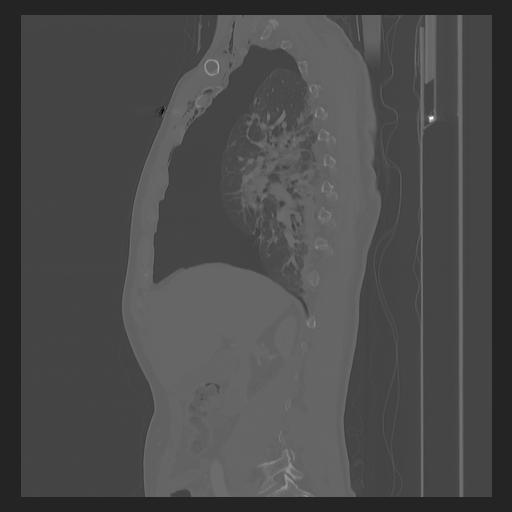

33 PULMON,CE,Sagittal,3.000,PULMON,Sagittal,